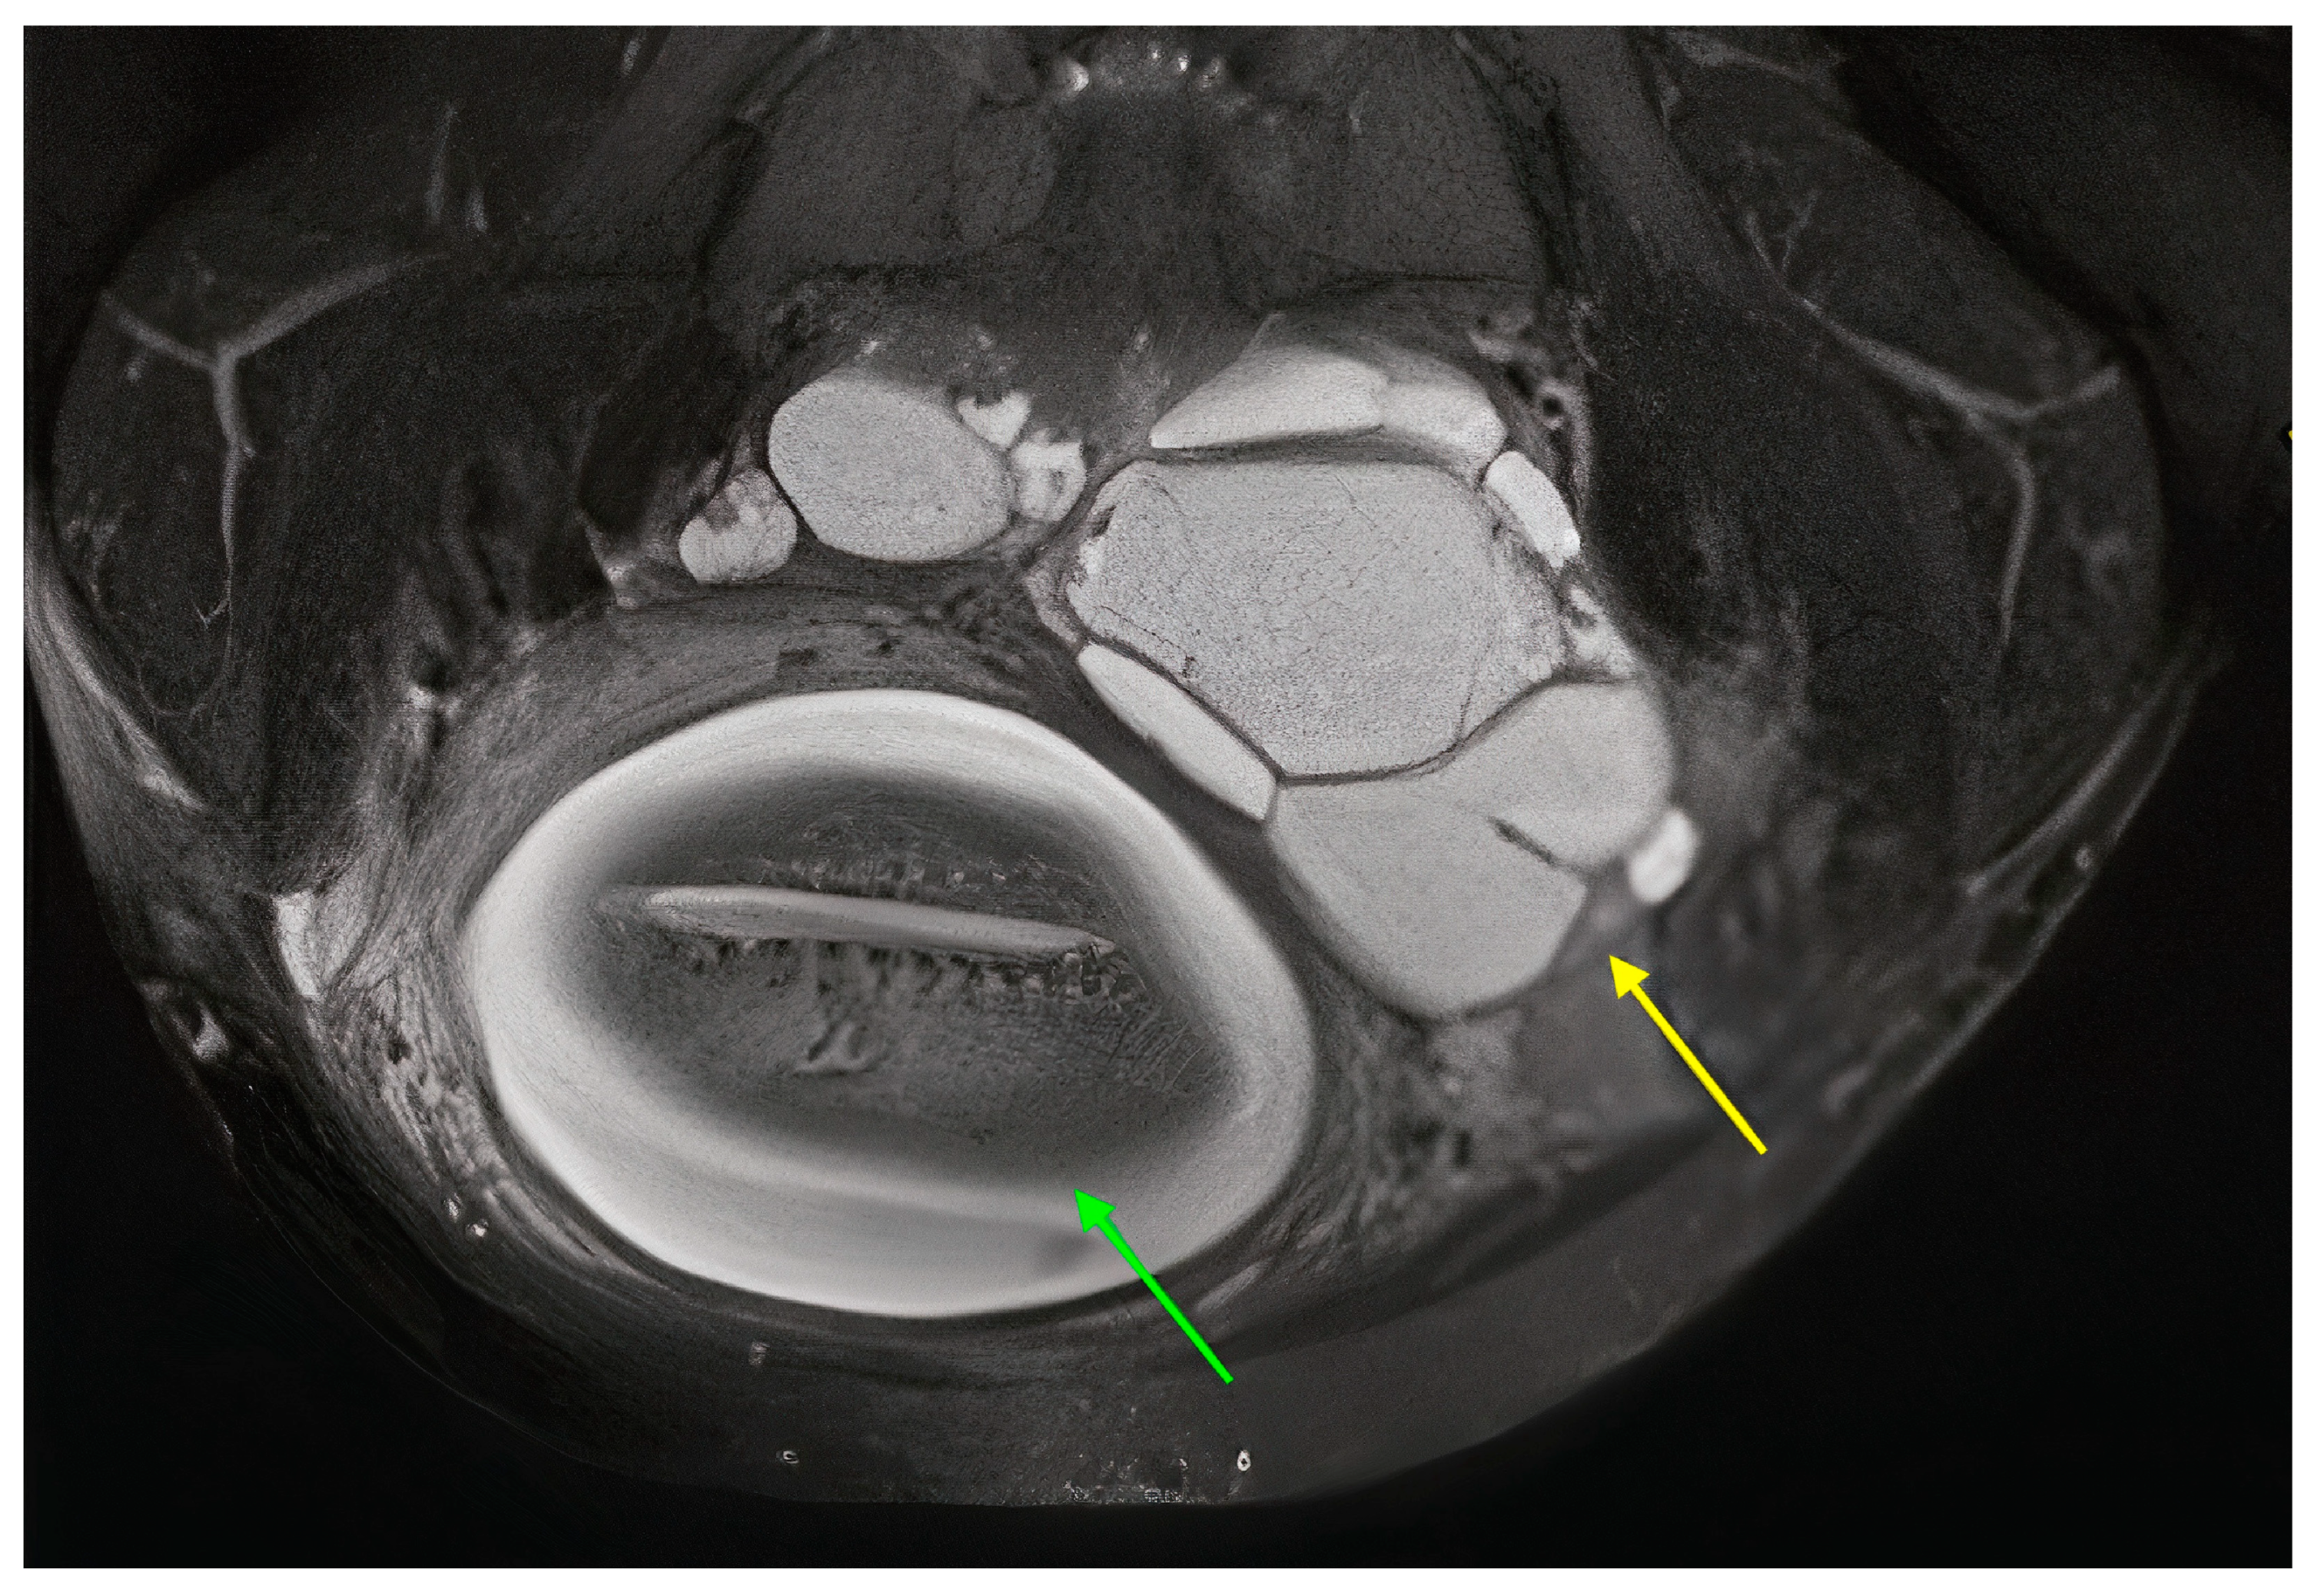

| Vivod | Abdominal pain | 28 | US + MR | 140 | 801 |